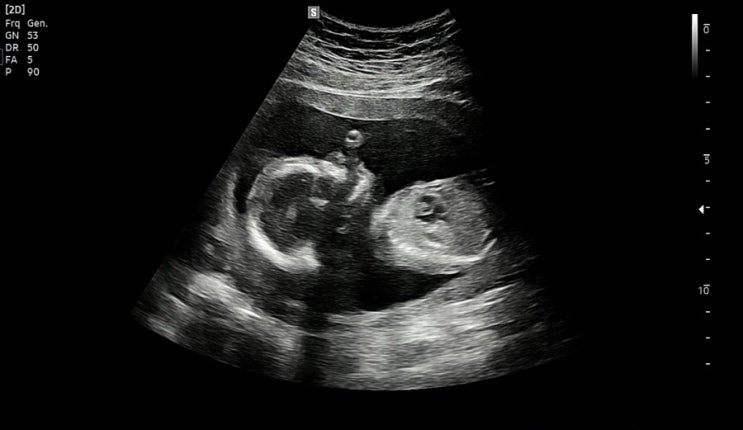

#진주참조은산부인과제왕후기 38주가 되니 아기가 많이 커져 태동도 강해지고 방광을 건들이는건지 ㅋㅋㅋ...

[임신기록]33주~37주 선택제왕 전 마지막 검진

#임신막달증상 무사히 접어든 33주 배가 진짜 남산만해지고 삼용이의 태동도 이전보다 훨씬 강해졌다. 가게...